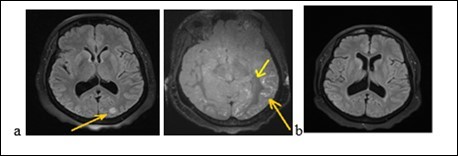

Mrs. A.S., a woman of 56, was admitted to hospital on february 9, 2018 for gradual onset in a three week, confusion, intense and diffuse headache with vomiting and photophobia. She treated the headache in automedication with a non-steroidal anti-inflammatory drug (NSAID, ibuprofen). The symptoms had worsened after 3 weeks with a serious trouble as her environment noted it. She had no story of vascular pathology. The neurological examination noted a neck stiffness, trouble and mutism. On the cardiovascular examination, the blood pressure was of 210/90 mm Hg. The examination of the other organs was normal. The blood count showed a leukocytosis at 12600 / mm3. The serum creatinine, glycemia, thyroid hormones and blood ionogram were normal. The cerebrospinal fluid (CSF) revealed 27cells/mm3 predominantly neutrophilic, with a normal glycorachia and hyperpropteinorachia of 0.6g/l. There was no germ in CSF after the preparations. The initial brain MRI (Figure 2a) had shown a range of edema in the left occipital lobe and diffuse enhancement of the leptomeninges. The electroencephalogram (EEG) had shown some slow waves in the left occipital lobe, with no epileptic figure or encephalopathy. The patient had been treated with nimodipine (60 mg every 8 hours) associated with analgesic drugs. The trouble and headache had decreased. The brain MRI (Figure 2b) at one (1) month had shown a complete decrease of the germs. The clinical and imagery findings fell on diagnosis of RPE syndrome.

Figure 2.Cerebral MRI showing a left occipital edema and a diffuse contrast enhancement of the leptomeninges (a) with complete decrease of the lesions after treatment (b)